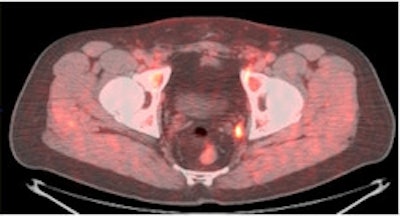

Another research study being presented at the SNM conference this week involves a new molecular imaging agent that could improve the diagnosis of recurrent prostate cancer and determine the best possible course of treatment for patients.

The agent, developed by Mark Goodman, MD, at Emory University in Atlanta, consists of a fluorine-based radioisotope paired with a synthetic amino-acid analog similar to the naturally occurring amino acid L-leucine (anti-F-18 FACBC).

| PET/CT with anti-F-18 FACBC (below) shows left obturator lymph node better than CT (top) and PET (above) images alone. |

Not only was the agent shown to be highly accurate in differentiating recurrent tumors in the prostate from metastatic cancer, but researchers believe the agent could help change patient treatment and improve the prognosis for prostate cancer patients.